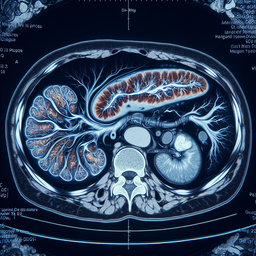

МРТ підшлункової залози

Магнітно-резонансна томографія (МРТ) підшлункової залози — це неінвазивний метод обстеження, який використовують для детального візуалізації структури підшлункової залози. Це дослідження проводять у таких випадках: